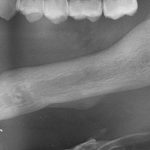

На первое место я бы поставил форму дефекта. Немного забегая вперед (а это будет темой следующей статьи), выбор метода наращивания костной ткани зависит, в основном, от двух параметров: биотипа кости и формы атрофического дефекта. Подробнее об этом я написал здесь>>. В общих чертах, некоторые случаи потери кости настолько сложные для наращивания, что сопоставляя стоимость, целесообразность и возможные риски, лучше отказаться от остеопластики в пользу какой-нибудь методики нетрадиционной сексуальной имплантации, типа «всё на четырёх», ультракоротких или базальных имплантов. Да-да, вы не ослышались! Базальные имплантаты — вполне себе метод, если отобрать их у доктора Иде, если использовать его по показаниям.

Как, например, в этом случае. Правда, это Ankylos: